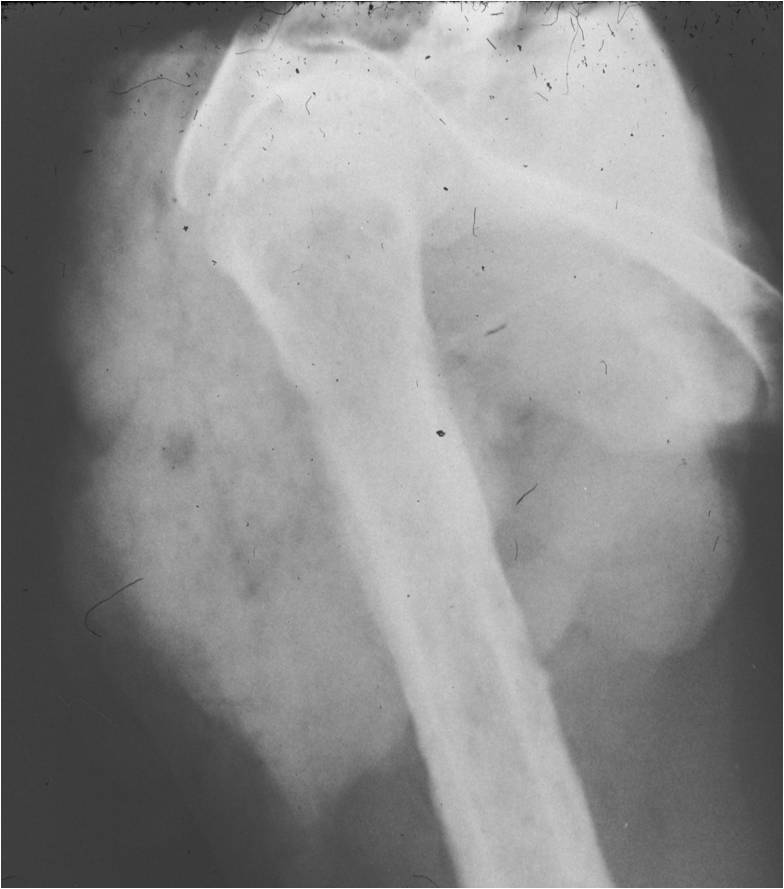

- Aggressive motheaten to permeative lesion

- Indistinct border in most cases

- Osseous destruction with a soft tissue component

- Chondroid matrix calcification may be present (60-70% of cases)

- Soft tissue mass